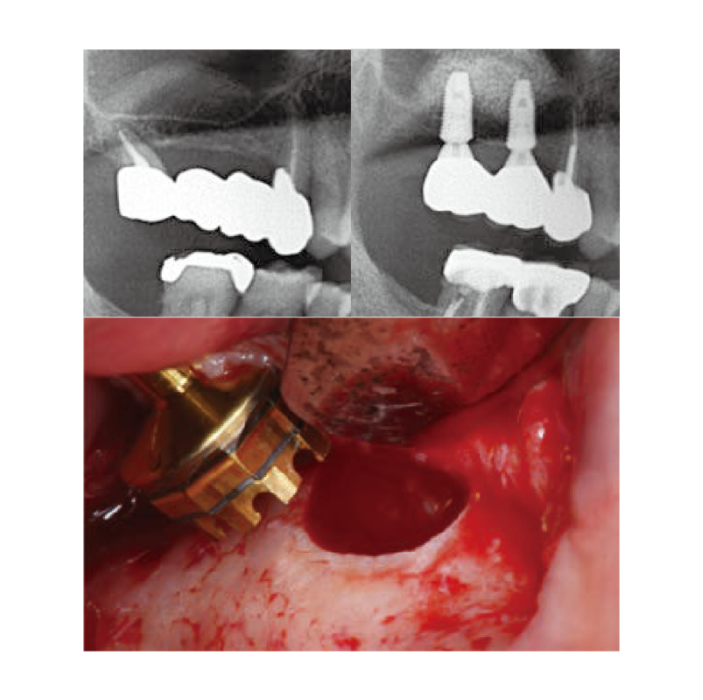

Clinical Cases

Crestal Approach -

Thin-out Technique -

Wall-off Technique